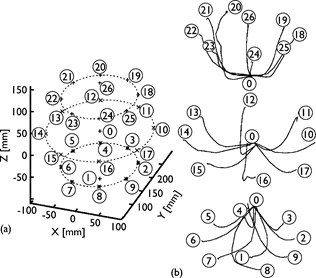

Profilo di Sintonizzazione Tridimensionale dell’Attività Corticale Motoria Durante i Movimenti del Braccio

Lo studio analizza l’attività della corteccia motoria primaria durante movimenti tridimensionali del braccio, mostrando una correlazione tra l’attività neuronale e quella muscolare, suggerendo che la codifica motoria dipende direttamente dai parametri muscolari e articolari.